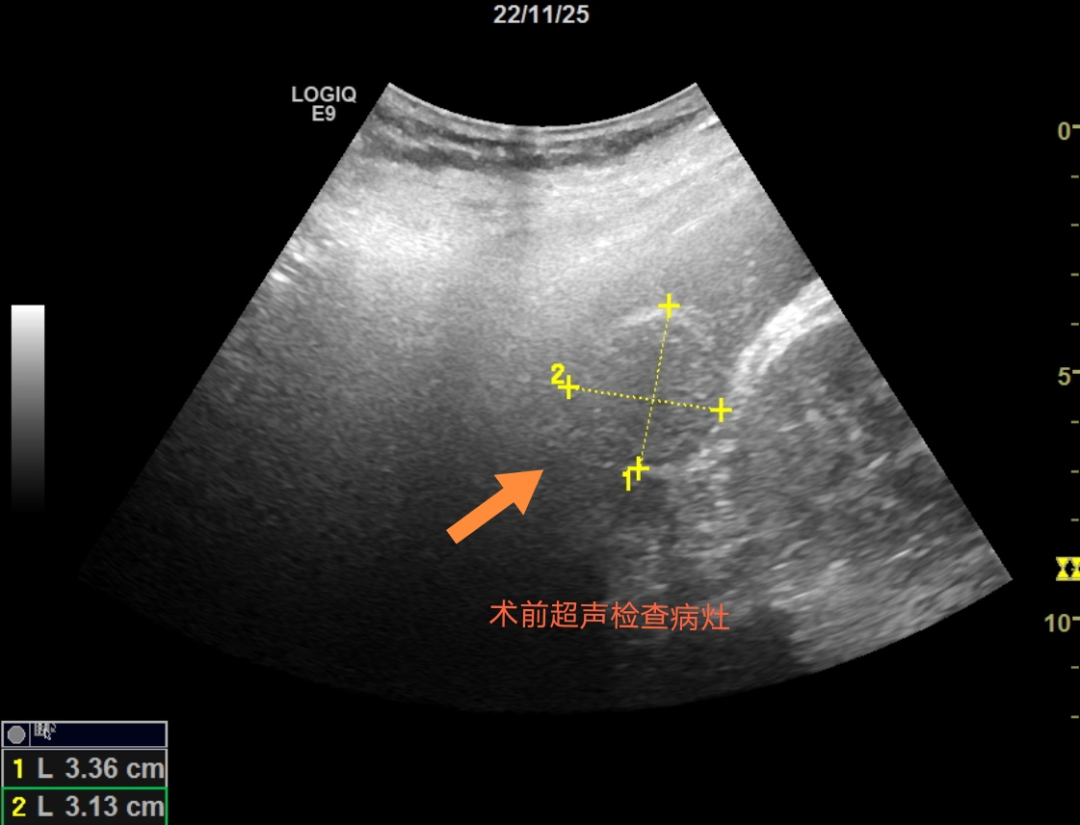

前不久,P女士在结肠癌术后进行腹部超声复查时发现肝脏上有三个低回声结节,再通过增强CT检查后医生结合病史考虑为肝脏转移灶。这样的结果,对P女士来说无疑为雪上加霜,想到自己去年才进行过一项大手术,难道还要再手术一次吗?对此,P女士及其家人感到迷茫。

察觉到P女士的顾虑以及她不想再进行二次手术的意愿后,消化内科的管床医生多次与任宏义谈论病情,在请教罗鸿昌教授仔细评估后认为可以采用超声引导下微波消融技术治疗患者的肝脏转移灶,而且术后恢复快,疗效好。这对于P女士及家属来说无疑是最好的消息。任宏义向患者及家属详细介绍了微波消融的方法、风险、注意事项及并发症等,罗鸿昌教授和任宏义对P女士的病情进行了术前讨论及严谨的手术设计